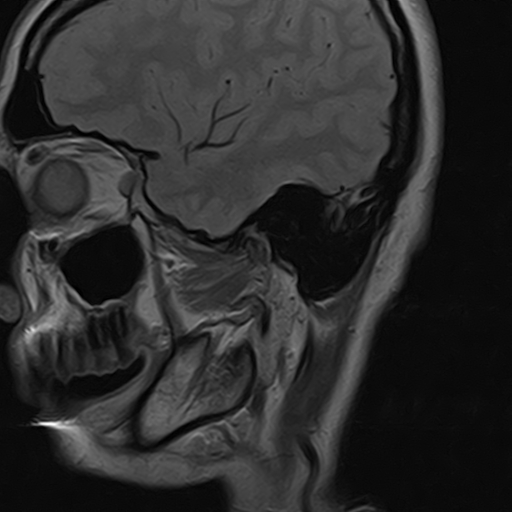

Височно-нижнечелюстной сустав является парным комбинированным суставом и имеет сложное строение. В него входят суставные ямки височной кости, суставные головки нижней челюсти и расположенные между ними хрящевые пластинки – мениски, выполняющие роль амортизаторов.

Чаще всего дисфункция височно-нижнечелюстного сустава обусловлена внутренним повреждением, смещением мениска и суставной головки нижней челюсти. Для определения степени смещения внутрисуставных структур выполняется функциональная проба с проведением МРТ в двух положениях:

• с закрытым ртом;

• с открытым ртом.

Магнитно-резонансная томография является наиболее точным и эффективным методом диагностики поражения височно-нижнечелюстных суставов, так как позволяет получить детальную информацию о состоянии не только костей, но и связочного аппарата, хрящей, менисков, жевательных мышц, окружающих мягких тканей.

При проведении магнитно-резонансной томографии на изображениях визуализируются: височная кость, головка мыщелкового отростка нижней челюсти, суставная щель. Помимо костных структур МРТ позволяет оценить состояние мягких тканей – внутрисуставного диска и связочного аппарата височно-нижнечелюстного сустава, жевательных мышц.